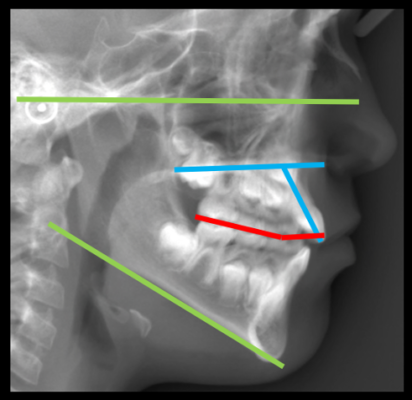

Reference planes used to evaluate the facial divergence. Fh, Frankfurt ...